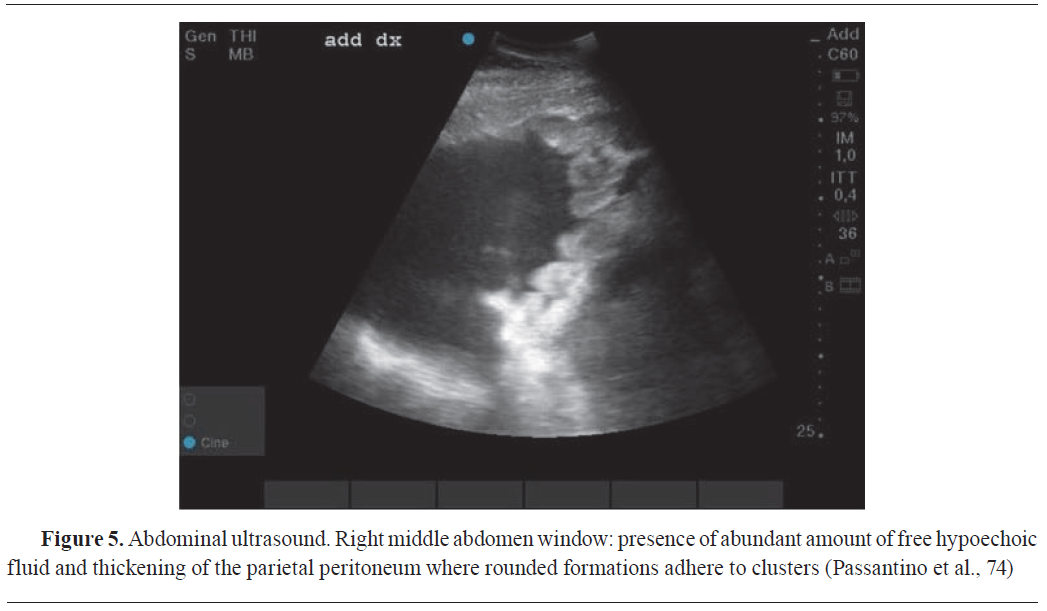

DIAGNOSTIC USES OF COMPUTED TOMOGRAPHY (CT) IN VETERINARY ONCOLOGY

Computed tomography (CT) has emerged as an indispensable tool in veterinary oncologic practice, offering precise tumour staging and dependable evaluation of chemotherapeutic response during follow-ups. Increasingly, CT plays a pivotal role in preoperative planning, enabling surgeons to evaluate tumour size and determine the feasibility of complete resection (

Fig. 6) (

87,

88). CT imaging also plays a crucial role in radiotherapy treatment planning (

63,

89). The strength of CT scanning lies in its high spatial resolution, allowing for anatomical characterization of neoplasms (

90).